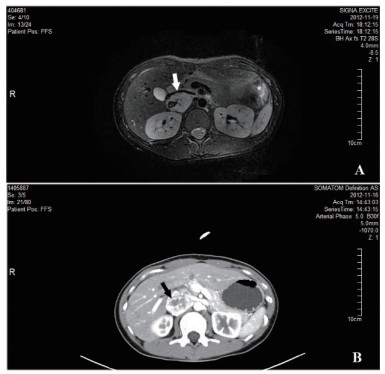

1 资料与方法患者1,女,22岁,因“发现肾上腺占位10 d”入住我院泌尿外科,无头痛、心悸、大汗,无高血压、低血钾,无满月脸、水牛背、皮肤紫纹,无月经紊乱等不适。完善皮质醇节律及醛固酮肾素比值后未见明显异常,尿香草扁桃酸(vanillylmandelic acid, VMA):26.20(0.1-68.6)μmol/24 h。肾上腺增强MRI:右侧肾上腺区域见类圆形等T1长T2异常信号影,大小约29 mm×37 mm,嗜铬细胞瘤可能性大(图 1A)。增强CT:右侧肾上腺见肿块影,大小约38 mm×29 mm,嗜铬细胞瘤可能(图 1B)。全麻下行腹腔镜下右肾上腺肿瘤切除术,手术过程顺利,术中血压心率平稳。手术病理:(右肾上腺)嗜铬细胞瘤。术后患者无明显不适,血压平稳,出院后未予特殊治疗。术后20天患者出现头痛,伴头晕、恶心呕吐,四肢抽搐2次,抽搐时伴双眼上视,至我院急诊就诊。查体:体温37.7℃,脉搏140次/min,血压205/148 mmHg,心律齐,双下肢无水种。辅助检查:血甲氧基去甲肾上腺素:111.3(< 112) pg/mL,血甲氧基肾上腺素:54.8 (< 61)pg/mL,尿VMA:56.20(0.1-68.6)μmol/24 h。心电图:窦性心动过速,下壁异常Q波伴ST段抬高改变,前侧壁、高侧壁ST段压低。头颅MRI:两侧枕顶叶及部分额叶皮质、左侧尾状核头肿胀伴信号异常,考虑可复性后部性脑白质病综合征可能。间碘苄胍(metaiodobenzylguanidine, MIBG)显像:肾上腺髓质显像未见明显异常。入院后予乌拉地尔、硝酸甘油静脉维持控制血压,血压稳定后逐渐减量,加用多沙唑嗪、厄贝沙坦。1周后患者症状缓解,血压平稳,复查头颅MRI未见明显异常。出院后继续口服多沙唑嗪、厄贝沙坦治疗。半年后逐渐停药,血压监测平稳。

图 1 肾上腺增强MRI:右侧肾上腺区域见类圆形等T1长T2异常信号影,大小约29 mm×37 mm,内部信号欠均匀,边缘光整,下腔静脉受压前移,增强后病灶明显持续性强化,嗜铬细胞瘤可能性大(箭头)。 B:肾上腺增强CT:右侧肾上腺见肿块影,大小约38 mm×29mm,内部密度不均,增强扫描呈明显不均匀强化,边界尚清,下腔静脉受压前移,嗜铬细胞瘤可能(箭头) |